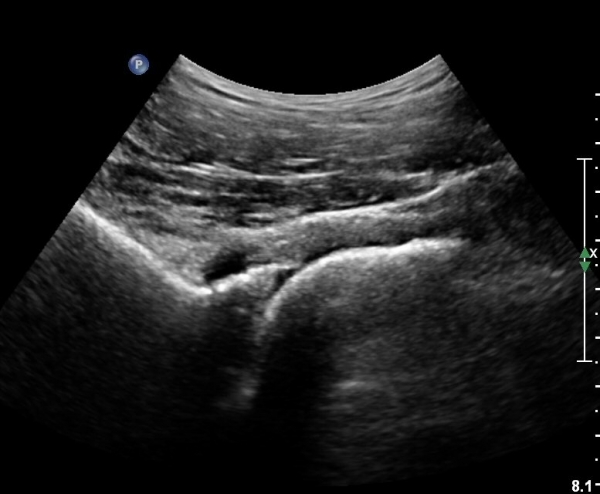

[¾ûµ¢ÀÌ] ¾ûµ¢ÀÌ °üÀý¼ø ÆÄ¿­ÀÇ ÃÊÀ½ÆÄ°Ë»ç(ultrasonography of labrum tear of hip joint)

ÃÊÀ½ÆÄ °Ë»ç

Sonography of the Acetabular Labrum Visualization of Labral Injuries During Intra-Articular Injections

What is the role of clinical tests and ultrasound in acetabular labral tear diagnostics?

Sonographic evaluation of anterosuperior hip labral tears with magnetic resonance arthrographic and surgical correlation.